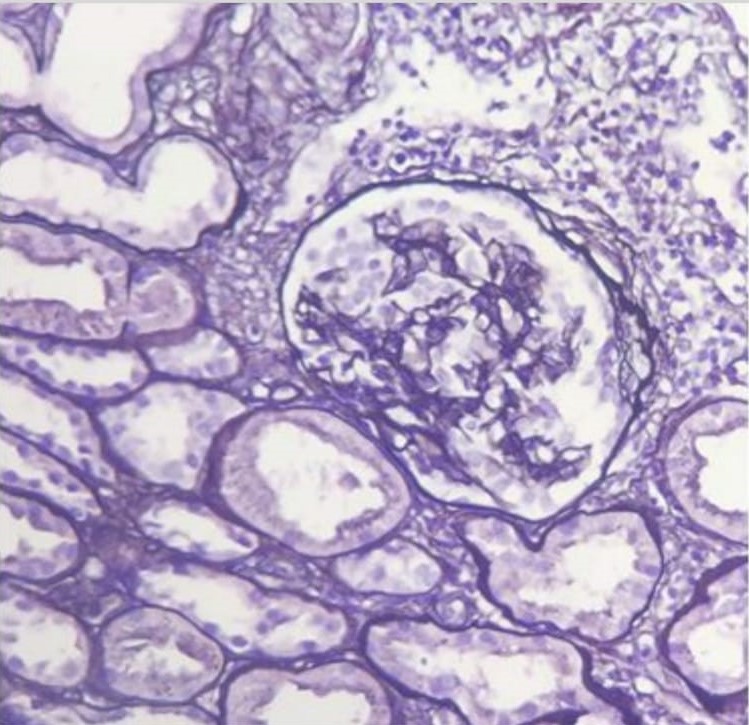

Results: 30-year-old male patient with history of nephrotic syndrome with hematuria and hypertension, creatinine of 1.5 mg/dl. The biopsy showed extra-capillary nephropathy with epithelial crescents, he received treatment with corticosteroids and cyclophosphamide, despite of what he evolves with a fall of glomerular filtration rate and dyalisis requirement in 2014. In December 2020 the patient receives a kidney transplantation from a deceased donor. He evolved with delayed graft function with dialysis requirement, hypertension and microhematuria. The first biopsy showed borderline cellular rejection; he received treatment with methylprednisolone iv. A second biopsy was performed and it reported nephroangioangiosclerosis and acute tubular necrosis (creatinine 8.07 mg/dl, urea 262 g/dl, and hematuria); subsequently, nitrogen values start to decrease and the patient is discharged. After 45 days, creatinine continued to drop to a minimum of 2mg/dl and proteinuria began to increase to 15g/day. After requesting the blocks of the 2014 biopsies for review, we concluded that the couse or end stage renal disease was a collapsing glomerulopathy and, in view of the increase in proteinuria (maximum of 15.7 g/d), we suspected that there was a recurrence of an underlying disease. We performed a third biopsy: glomeruli with hypertrophy and focal podocyte hyperplasia. The patient received treatment with methylprednisolone iv, plasmapheresis and rituximab. Creatinine decreased to 0.9mg/dl and protein to less than 1 g.

Conclusion: Collapsing glomerulopathy is histologically defined by segmental or global capillary collapse and hyperplasia and hypertrophy of epithelial cells in the urinary space. This exaggerated cellular hyperplasia may resemble a crescent, sometimes leading to misdiagnosis. Recurrences of glomerulopathies in kidney grafts represent a challenge; therefore, knowing the cause of end-stage renal disease prior to transplantation is fundamental to be able to plan ahead these clinical situations.